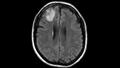

وأظهر فحص التصوير بالرنين المغناطيسي لدماغ المرأة ضوءًا خافتًا غير واضح في الفص الجبهي الأيمن.

وأوضح طبيب الأمراض المعدية في الجامعة الوطنية الأسترالية ومستشفى كانبيرا، "سانجايا سيناناياكي"، إن هذا الضوء الذي ظهر أثناء عمليات المسح يمكن أن يكون سرطانا أو جيبا من القيح "إفرازات بيضاء أو صفراء أو خضراء تتكون من خلايا الدم البيضاء الميتة والبكتيريا".